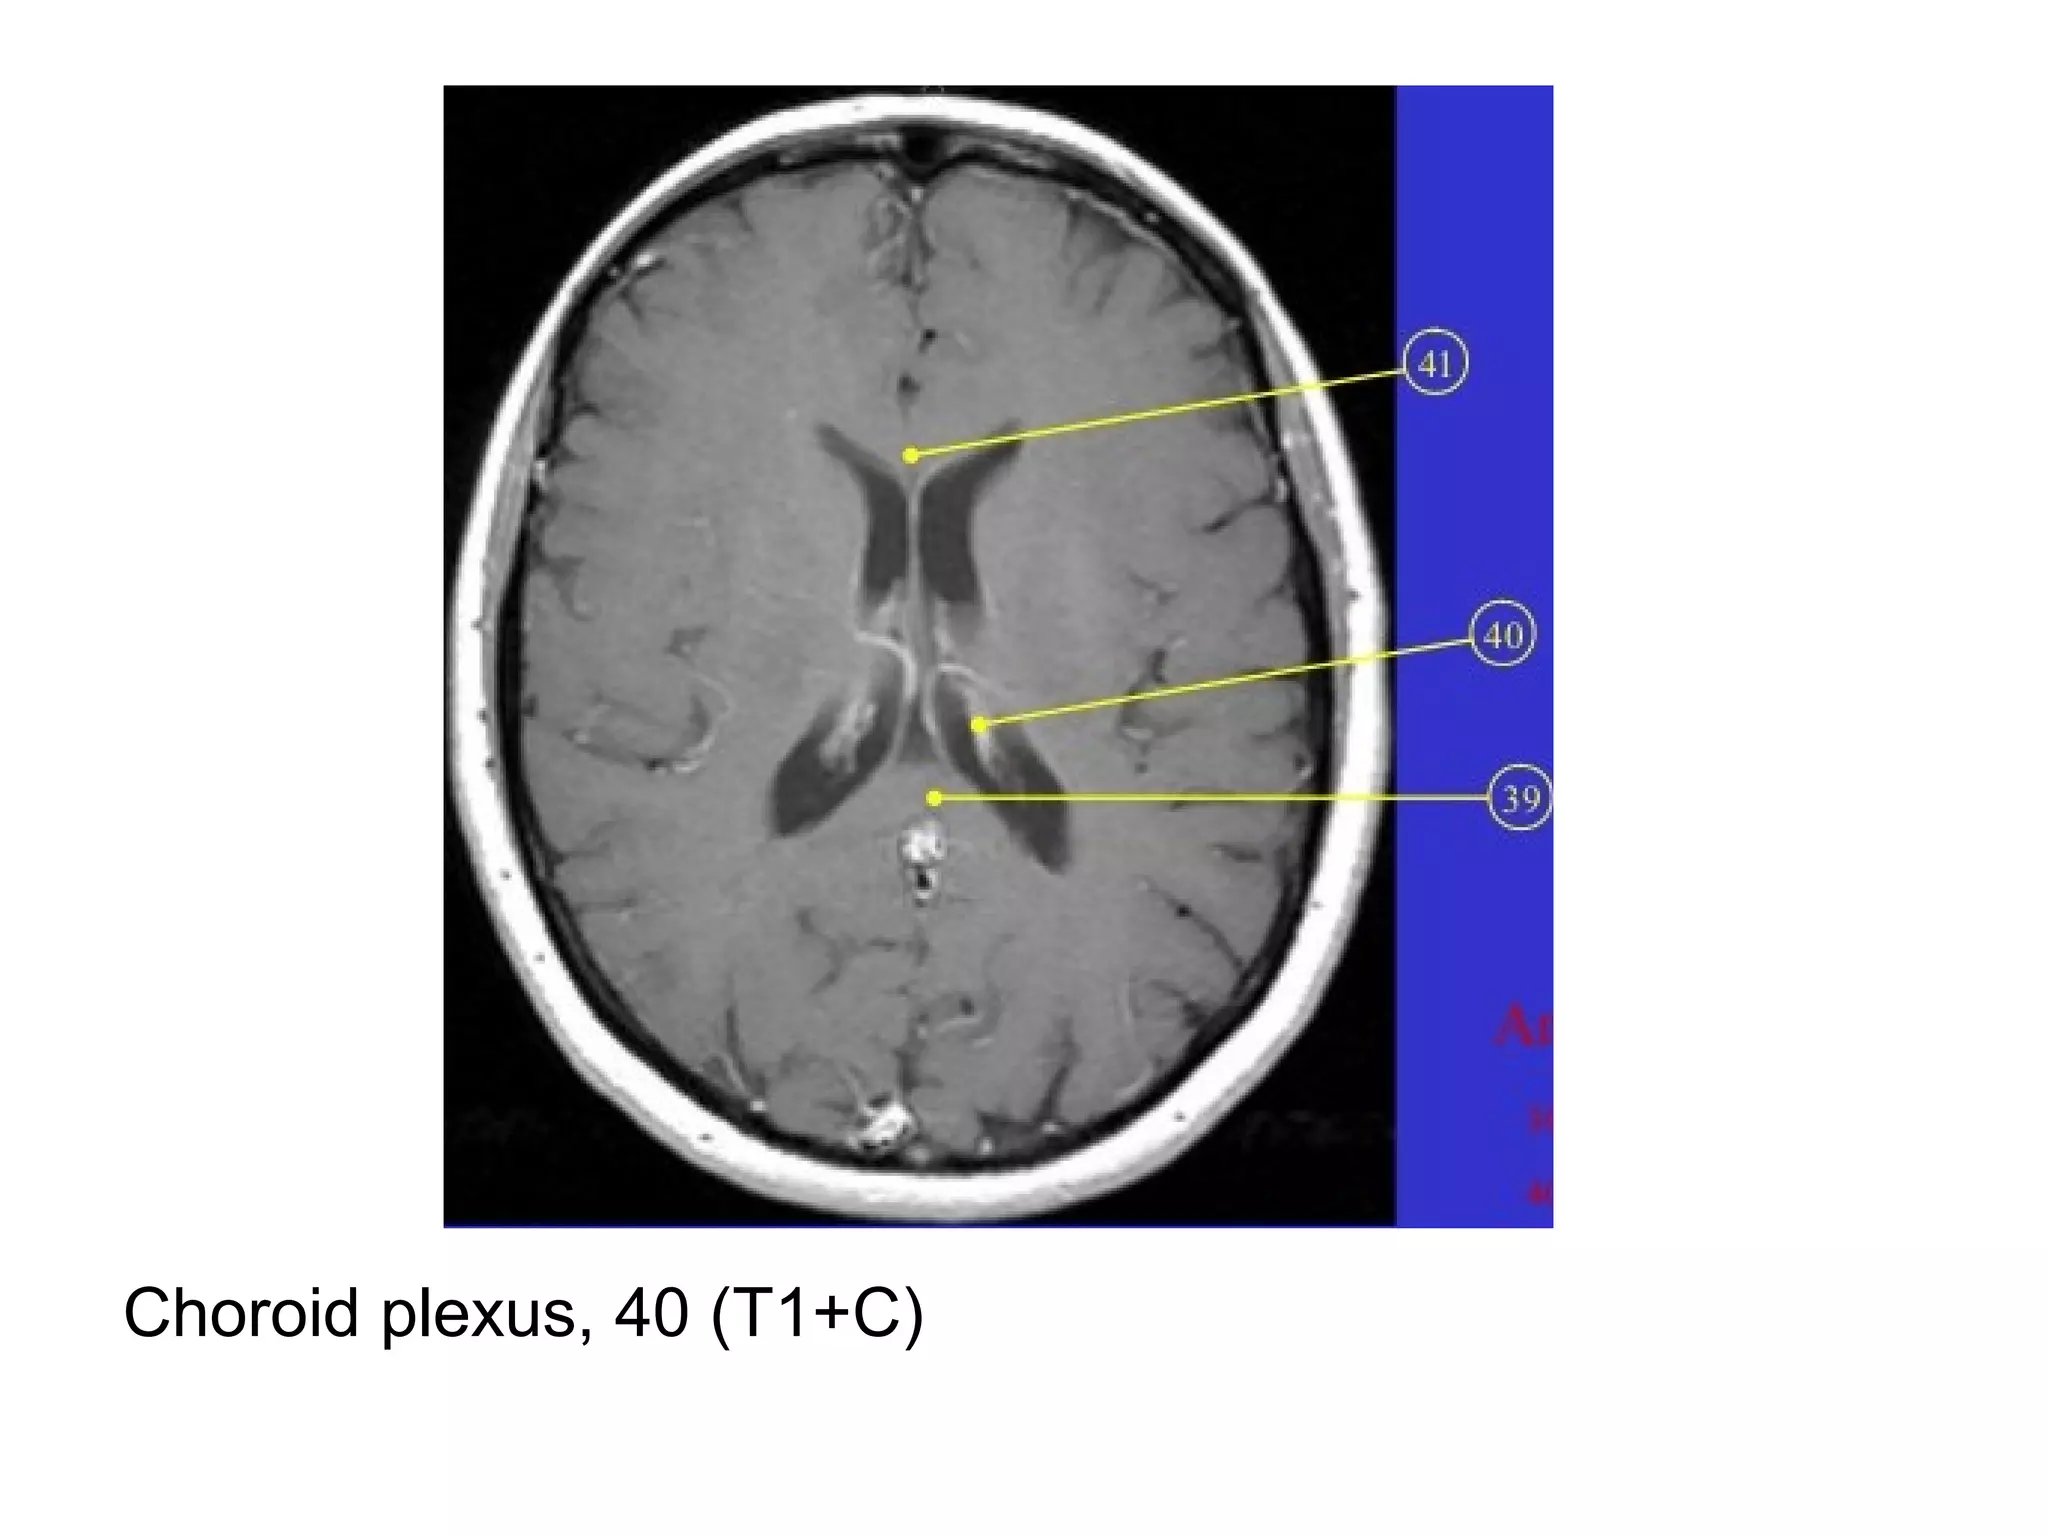

-Several CNS regions don’t have a BBB and therefore

a) Choroid plexus

Choroid plexus, 40 (T1+C)

-Several CNS regionsdon’t have a BBB and therefore normally enhance : a) Choroid plexus b) Pituitary & pineal glands c) Tuber cinereum (controls circadian rhythm, located in the inferior hypothalamus) d) Area postrema (controls vomiting, located at inferior aspect of the 4th ventricle) -The dura also lacks a BBB , but doesn’t normally enhance -Intracranial enhancement may be intra or extra-axial, extra-axial structures that may enhance in pathologic conditions include the dura (pachymeninges) & arachnoid (leptomeninges)